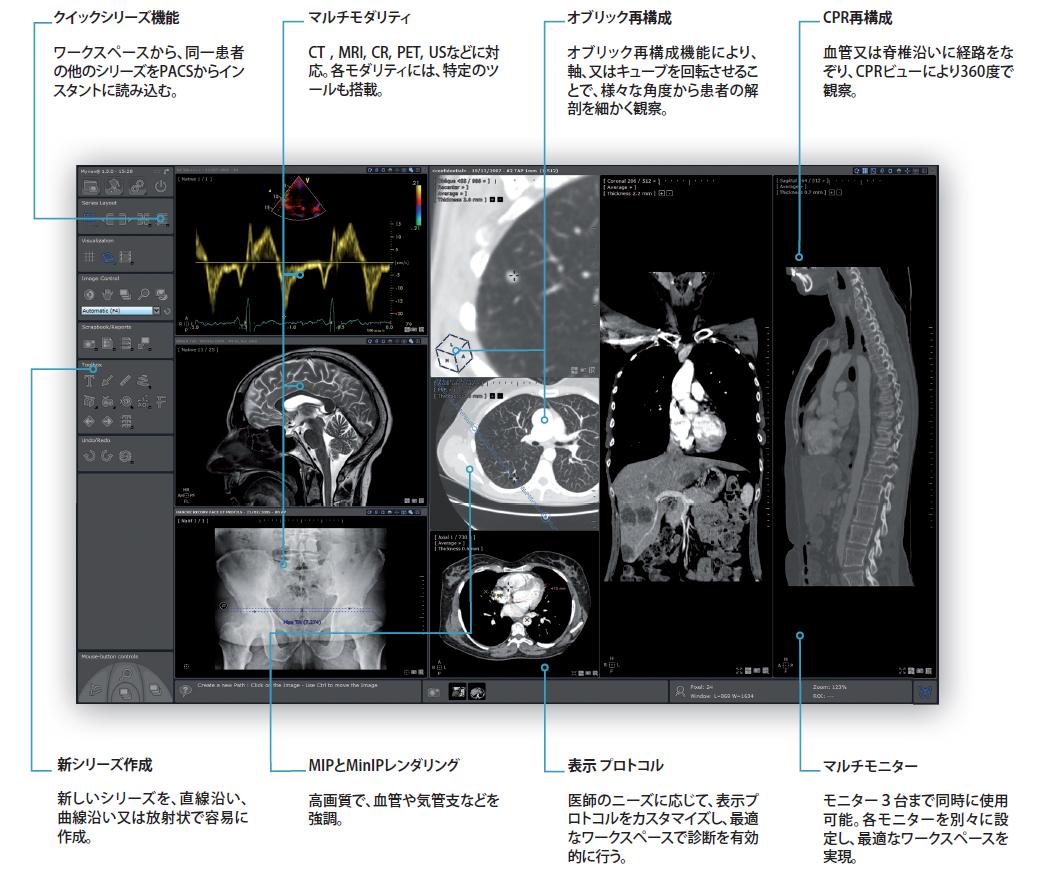

Myrian®Advance 基本機能のプラットフォームソフトウェア

病院、又は自宅でも、ラップトップもしくはPACSで、診断用の最先端マルチモダリティワークステーション

Myrian®Advanceは、マルチモダリティ診断ワークステーションとして開発され、最新の機能を搭載しています。最適化されたワークスペースで、診断に必要なツールの全てを提供します。最高の読影効率を目指したカスタマイズできるプロトコルで、ワークスペースを自動的に整理することが可能です。また、MPR、MIP、MinIP、オブリック、複数シリーズの連動表示機能などを搭載していることで、読影のパーフォーマンスを向上させることが可能です。読影室、会議室、又は自宅でも、同一患者のデーターの読影を行うことが可能です。日常臨床をより効率的に行うための、PACSと連携できる新世代のワークステーションを、お手頃な値段で実現しました。